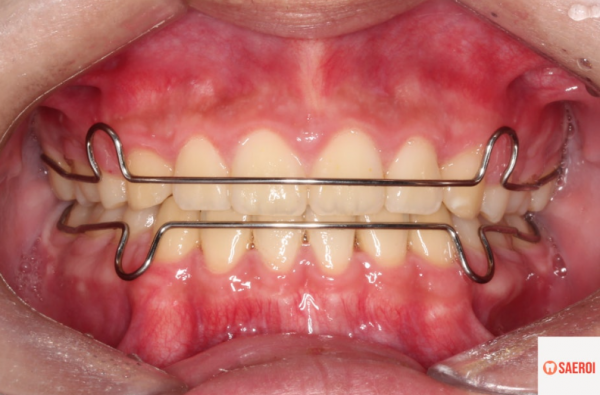

이처럼 생긴 유지장치를 교정종료 후

껴주셔야 합니다.

출처 입력